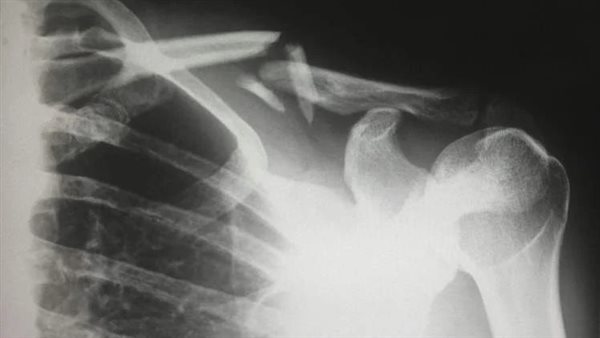

في واقعة طبية نادرة، أصيبت امرأة صينية تبلغ من العمر 48 عامًا بكسر في العظام خلال تقلبها في السرير، نتيجة إصابتها بهشاشة عظام شديدة ناجمة عن نقص حاد في فيتامين د، والذي عزاه الأطباء إلى الإفراط في استخدام واقي الشمس وتجنّب التعرض لأشعة الشمس منذ الطفولة، وذلك وفقًا لـ أوديتي سنترال.

ووفقًا لتقرير صادر عن مستشفى شيندو للطب التقليدي في مدينة تشنغدو، فإن الفحوصات أظهرت تراجعًا ملحوظًا في كثافة العظام لدى السيدة، ما جعل عظامها هشة إلى درجة أنها تعرضت للكسر من حركة بسيطة. وأفاد الدكتور لونغ شوانغ، المشرف على حالتها، أن المريضة اعتادت على تغطية بشرتها بشكل دائم وحرصت على استخدام واقي الشمس في جميع تنقلاتها، ما حرم جسدها من المصدر الأساسي لإنتاج فيتامين د.